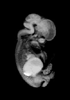

Carnegie Stage 22 (54 post-ovulatory days)

Most embryos at stage 22 are approximately 54 postovulatory days old and measure 25-27 mm in length. Distinguishing criteria for this stage include clear formation of the external ear, the hands begin to extend ventrally beyond the body wall, the fingers of one hand may overlap the fingers of the opposite hand, thickened eyelids just begin to cover the outer margins of the eye, and the superficial vascular plexus of the head now extends about three-quarters of the way above the eye-ear level.